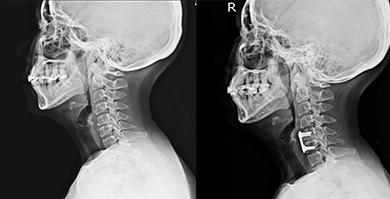

Injection-based procedures are performed with image guidance such as ultrasound and fluoroscopy.

Regenexx SD injectate is bone marrow concentrate, which contains stem cells. This procedure is performed over the course of three days and these cells are harvested and reinjected on the same day. These repair cells from your own body live inside all of us in various tissues, poised to leap into action to repair damage as it occurs. As we age or have big injuries, we may not be able to recruit enough of these cells to the site to fully repair the area. This procedure helps overcome this problem by harvesting bone marrow from an area of the back of the hip that contains a dense population of these important cells and then concentrating those cells before precisely injecting them into the injured area using advanced imaging guidance. The goal of the procedure is to reduce pain and improve function by promoting the body’s own ability to heal naturally. This patented bone marrow concentrate protocol can be used for a wide range of orthopedic conditions. Your doctor will evaluate your condition and your imaging to determine whether a bone marrow concentrate or platelet-based treatment is the best option for your orthopedic condition.

Platelet rich plasma (PRP) and platelet lysate are platelet procedures that contain healing growth factors from your own blood that promote your body’s natural ability to repair itself. The use of PRP to treat joint, tendon, ligament, and muscle injuries is becoming well known, thanks to exposure from professional athletes. Platelet injections have a stimulating effect on the repair cells within the targeted area, making those cells work harder to perform their natural job of healing the body. For most patients the recommended SCP or PL protocol involves a blood draw and an injection on the same day. Like all procedures using Regenexx SCP injectate, they are performed with high-level imaging guidance to ensure the most accurate placements of cells into the desired area. These advanced platelet procedures are more concentrated and purer than PRP created by the automated machines used at most regenerative medicine clinics, increasing its ability to stimulate the body’s natural healing response. Platelet procedures are commonly used for soft tissue injuries, mild arthritis, spine conditions, and around nerves.